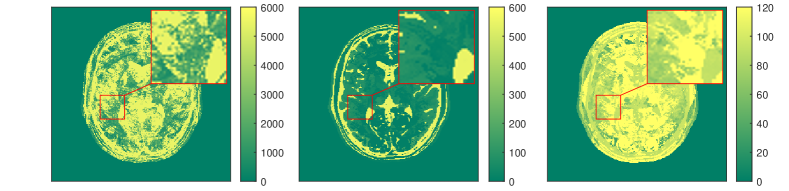

The results for each of the above mentioned algorithms can be found in Figures 3 and 4. We use the MRF reconstruction as initialization for the L-M algorithm, and compare that with the result of the BLIP algorithm when using a relatively refined dictionary. The advantage of integrated-physics approaches is evident by checking the reconstructions in Figure 3 as well as quantitatively by looking at the error maps in Figure 4. In this example, we have used a time series of the 1/8 Cartesian-subsampled k-space data (Fourier coefficients of magnetizations) of length 40. In the original MRF algorithm (typically requiring a large time series of k-space data), this test setting is far from yielding a reasonable result, while BLIP has improved a little by enforcing the projection to the Bloch manifold. But still one observes deficiencies. The method with integrated physics, however, appears to be efficient and it returns the best results among the three methods.

Here, is the projection operator onto the feasible set . The operator is the Frechét derivative of the parameter-to-solution map of the Bloch equations, and is the generalized inverse of the sub-sampled Fourier transform, i.e. , where is the zero filling operator, and is the inverse Fourier transform. For comparing a variety of algorithms for qMRI, we present a set of examples in the following. Our tests are based on synthetic data from an anatomical brain phantom, publicly available from the Brain Web Simulated Brain Database [24, 48, 119]. More details on how to generate this data can be found in [57] or [52].